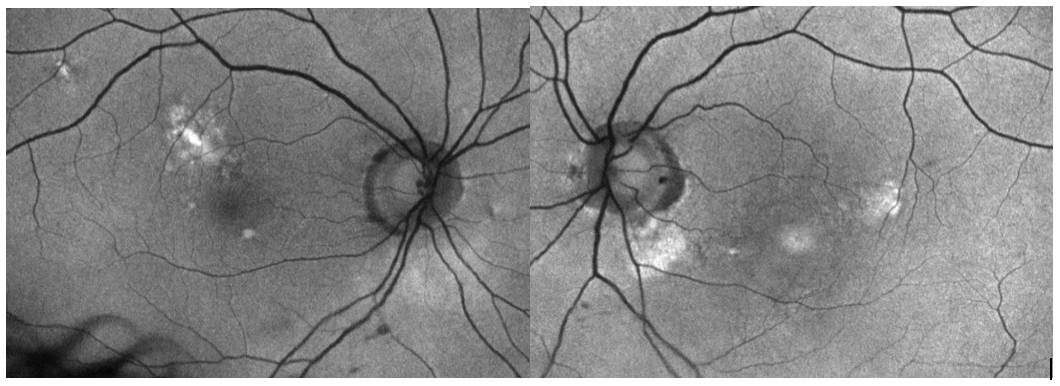

An 81-year-old white male presented with a complaint of gradual distortion in their central vision. The patient’s referring ophthalmologist noted a concern for neovascular age-related macular degeneration. The patient’s visual acuity was 20/30 OD and 20/25 OS. OCT of the right eye showed RPE elevation consistent with drusen and highly reflective, subretinal lesion. OCT of the left eye demonstrated a larger, highly reflective and well-circumscribed, homogenous subretinal (pseudo-vitelliform) lesion with an underlying optically empty zone. Fundus autofluorescence (FAF) imaging disclosed hyperfluorescence corresponding to the areas of RPE irreuglarities and pseudovitelliform lesions in both eyes. Fluorescein angiography (FA) was performed to differentiate the optically empty zone from subretinal fluid associated with a choroidal neovascular membrane (CNVM). FA showed macular staining consistent with drusen and no hyperfluorescence consistent with leakage, indicating the absence of a CNVM. The patient was diagnosed with adult onset foveomacular vitelliform dystrophy with a plan to observe every six months.

Adult-onset vitelliform dystrophy generally onsets between the fourth and sixth decade. The disease course is slowly progressive but can result in significant vision decline in cases with development of CNVM or macular atrophy.1 Patients present with subretinal, well-circumscribed lesions that appear yellow on macular examination. Fundus autofluorescence shows increased autofluorescence corresponding to the lesion, and OCT reveals hyperreflective material between the ellipsoid zone and the retinal pigment epithelium. In later stages, the pseudovitellifom lesion may resorb, resulting in an optically empty zone within the pseudovitelliform lesion, reduction in size of lesion, and eventually RPE atrophy.2 The optically empty zone can resemble subretinal fluid, masquerading as wet macular degeneration. FA may be required to differentiate between CNVM and resorption of vitelliform lesion. Patients with pseudovitelliform lesions that present concurrently with subretinal drusenoid deposits may be at a higher risk of developing CNVM and/or macular atrophy.1